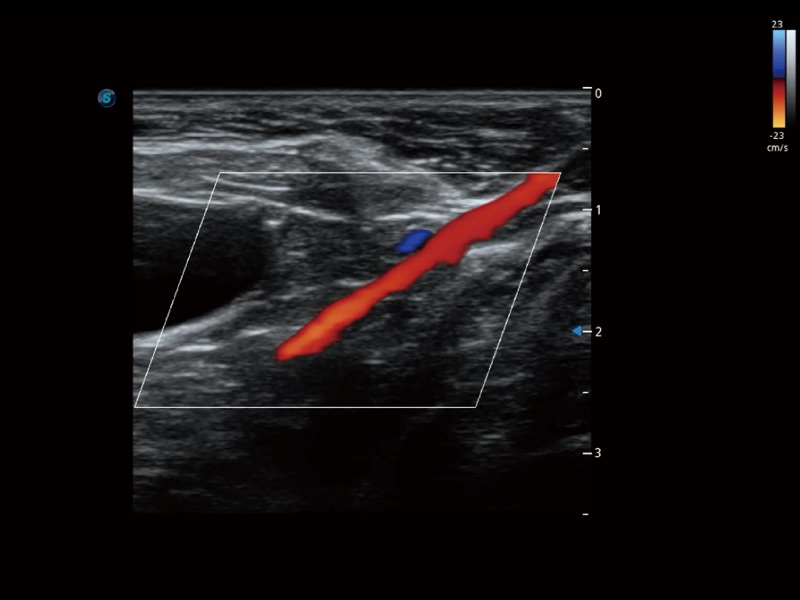

通过色彩血流和实时宽景相结合,可观察到完整的静脉或动脉的血流,方便医生检查。实时扫查过程中,如有任何操作失误也可以很容易地进行回扫擦除,而不会中断扫查。

ProPet 70 全新的动物超声智能软件和丰富的探头群,为动物医生提供了高清晰度和精细分辨率的图像,无论在宠物、马科、畜牧还是实验室动物等应用中都可以轻松应对,为您的日常工作带来满意的体验。